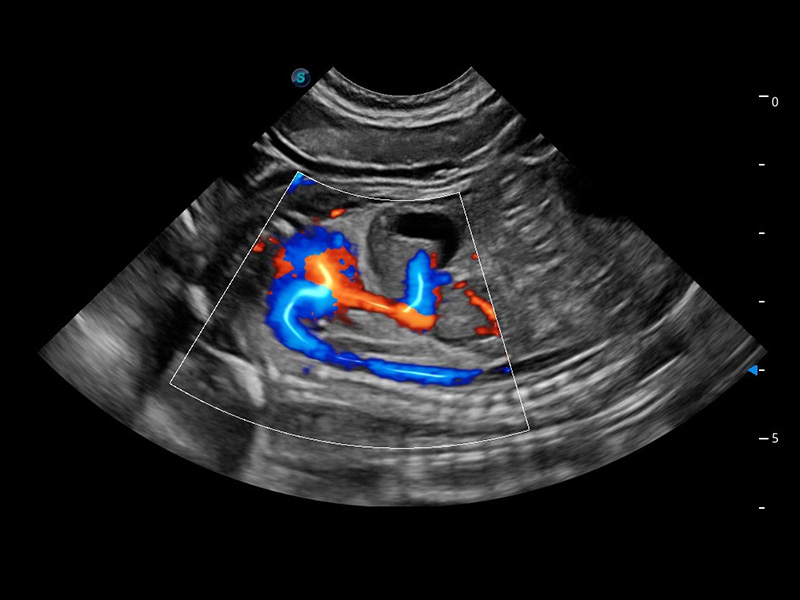

心脏解决方案

ProPet 60 配备了丰富的心脏探头群、先进的成像技术和专业的心脏测量工具,可帮助动物医生为不同体型和生理结构的动物提供心脏和心肌功能的全面评估。

优异的基础图像

(犬)四腔心血流